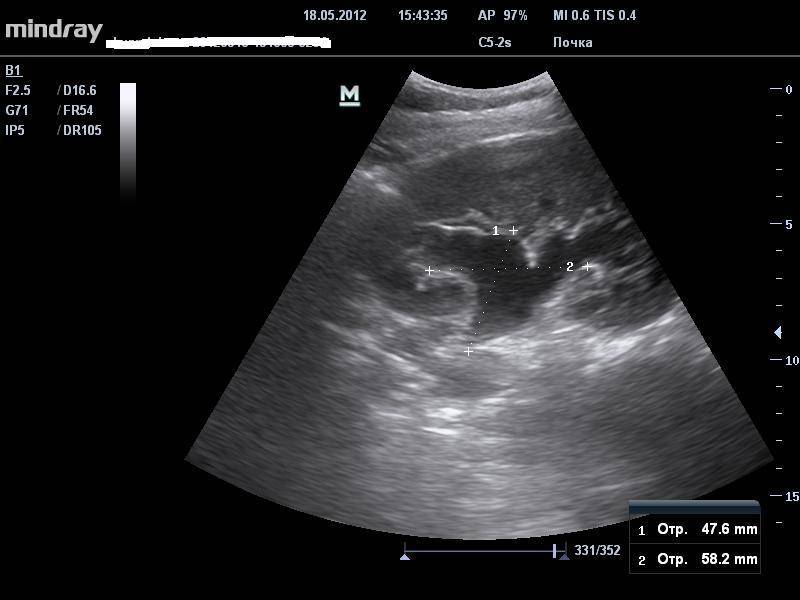

Интраренальная лоханка: рентгеновские снимки и примеры

Раздел: Фотоэссе